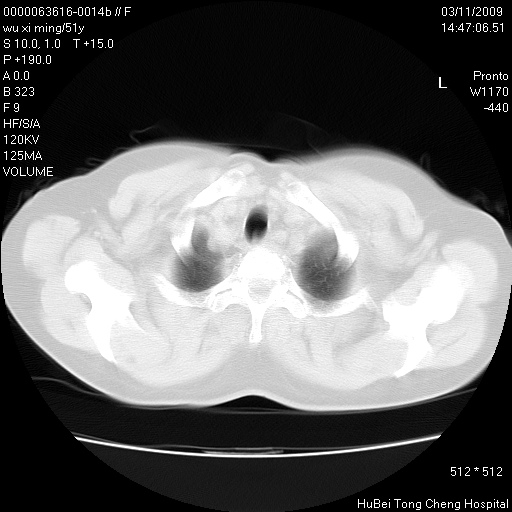

患者 女,51岁。因“胆囊炎,胆囊结石”,行常规术前胸部x线检查发现:右上肺结节病灶,建议行进一步检查。患者无咳嗽、咳痰及咯血等呼吸道症状,近期出现背部疼痛不适。

胸部ct轴位平扫(层厚10mm,螺距1.5,重建间隔10mm;部分层面:层厚3mm,螺距1.0,重建间隔3mm),图像如下:

考虑右肺癌肺内转移!

右肺周围型肺癌伴肺内转移信胸椎转移